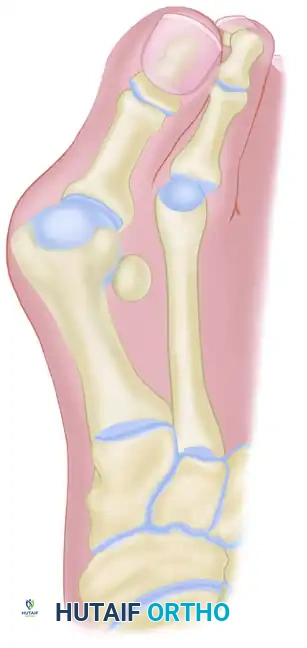

The pathogenesis of hallux valgus is characterized by the progressive failure of the medial stabilizing structures of the first MTP joint, leading to a cascade of biomechanical derangements.

The essential lesion is often debated—whether it originates as metatarsus primus varus (medial deviation of the first metatarsal) or lateral deviation of the proximal phalanx. Current evidence suggests that in adults, lateral deviation of the great toe is typically the primary event, followed by secondary medial angulation of the first metatarsal. Conversely, in juvenile and adolescent populations, metatarsus primus varus may be the primary structural anomaly.

* Abductor Hallucis: Normally a medial stabilizer, the abductor hallucis tendon slides plantarward beneath the metatarsal head. It loses its abducting moment and becomes a deforming force, contributing to the pronation and flexion of the hallux.

* Adductor Hallucis: Unopposed by the abductor hallucis, the adductor hallucis pulls the proximal phalanx further laterally.

* Extensor Hallucis Longus (EHL) and Flexor Hallucis Longus (FHL): As the MTP joint subluxates, these powerful extrinsic tendons bowstring laterally across the joint, acting as a bowstring that exponentially exacerbates the valgus deformity.

The sesamoids are embedded within the plantar plate and the tendons of the flexor hallucis brevis (FHB). They do not actively subluxate laterally; rather, the first metatarsal head drifts medially off the sesamoid apparatus.

As the metatarsal head moves medially, the sesamoid sling apparatus becomes a valgus deforming force, and the metatarsal rotates (pronates) on its longitudinal axis. The crista, which normally separates the medial and lateral sesamoid grooves, is eroded, leading to intractable pain and osteoarthritis if left uncorrected.